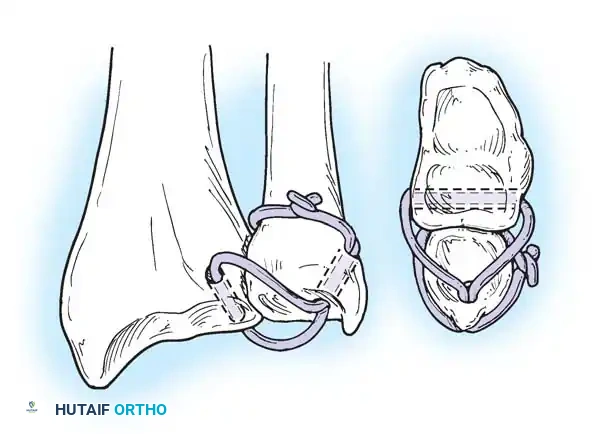

Preparation of the distal ulna: Drill holes are created at the fovea to facilitate transosseous suture passage for anatomic TFCC reattachment.

Transosseous Repair Technique:

1. Identify the foveal detachment arthroscopically or via an open dorsal ulnar approach.

2. Prepare the ulnar fovea down to bleeding bone using a burr or curette to stimulate a healing response.

3. Utilize a targeting guide to drill two converging osseous tunnels from the ulnar neck into the fovea.

Passing non-absorbable sutures through the osseous tunnels in the ulna to capture the peripheral edge of the TFCC.

- Pass strong, non-absorbable sutures (e.g., 2-0 FiberWire) through the TFCC using an outside-in or inside-out technique, then shuttle the suture limbs down the osseous tunnels.

The sutures are tied securely over the cortical bone bridge of the ulnar neck, restoring tension to the radioulnar ligaments.

- Tie the sutures over the ulnar cortical bridge with the forearm in neutral rotation to restore anatomic tension.